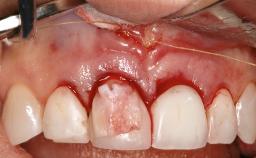

Peri-Implant Mucositis Associated with Misfit of a Cemented Restoration

A 37-year-old male patient was referred to the Department of Periodontology at the University of Bern, Switzerland, by a private dentist. Tooth 21 had been lost due to trauma and had been replaced with an implant and a cemented single crown. The tapered-effect tissue-level implant had a diameter of 4.1 mm, a length of 12 mm, and a sandblasted and acid-etched (SLA) surface (Straumann Dental lmplant System; Institut Straumann AG, Basel, Switzerland). The metal-ceramic crown had been cemented permanently, leaving a submucosal gap between the implant shoulder and the crown margin. Absence of marginal bone loss apical to the polished transmucosal neck of the implant could be observed .